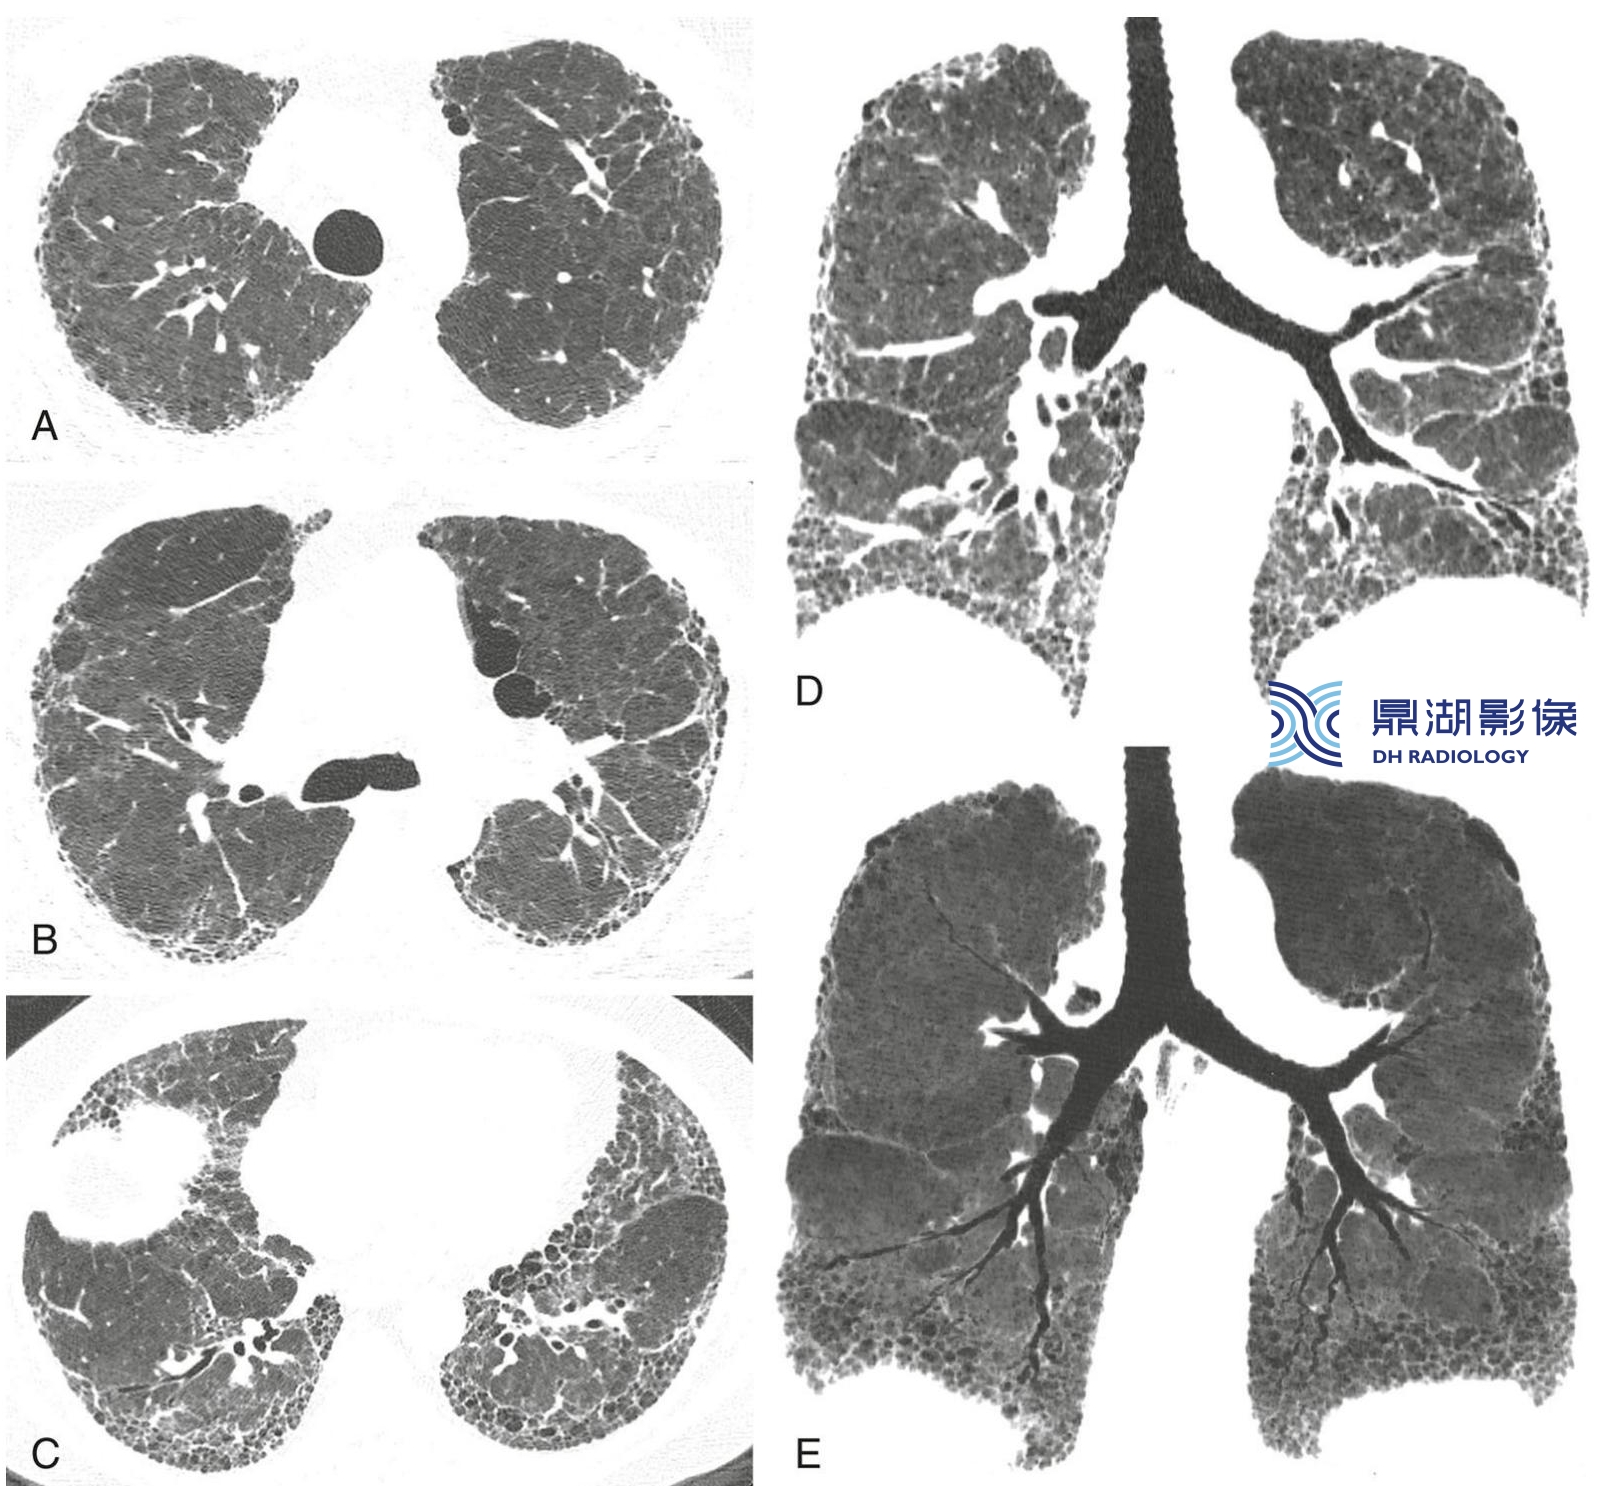

53d6375849f2940cc1f189ff2ae4a722.jpg

非特异性间质性肺炎的分布。

经上肺(A) 、中肺(B)及下肺(C)层面的HRCT图像显示分布在胸膜下和肺基底的不规则网状影及牵拉性支气管扩张。

冠状位重组(D)及冠状位最小强度投影(MIP)重组(E)图像证实病变分布在肺基底部。